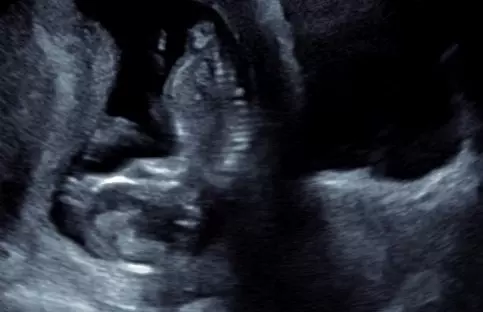

That’s what the team at FWPC provided. Between the research Fimbrez conducted and provided and the sonogram’s dating of Deanna’s pregnancy, there was likely a window of time so that the radiation treatment may not have had the impact the client, her physicians, and the father of the baby feared.

“She was about six-and-a-half weeks along when we did the ultrasound,” Fimbrez said.

Deanna made an appointment with a doctor Fimbrez had suggested and later learned Deanna felt “comfortable and more encouraged” after that appointment. She returned to FWPC for another ultrasound when she was 12 weeks along and hoped continued to soar, both for Fimbrez and for Deanna.

“We saw growth,” Fimbrez said.